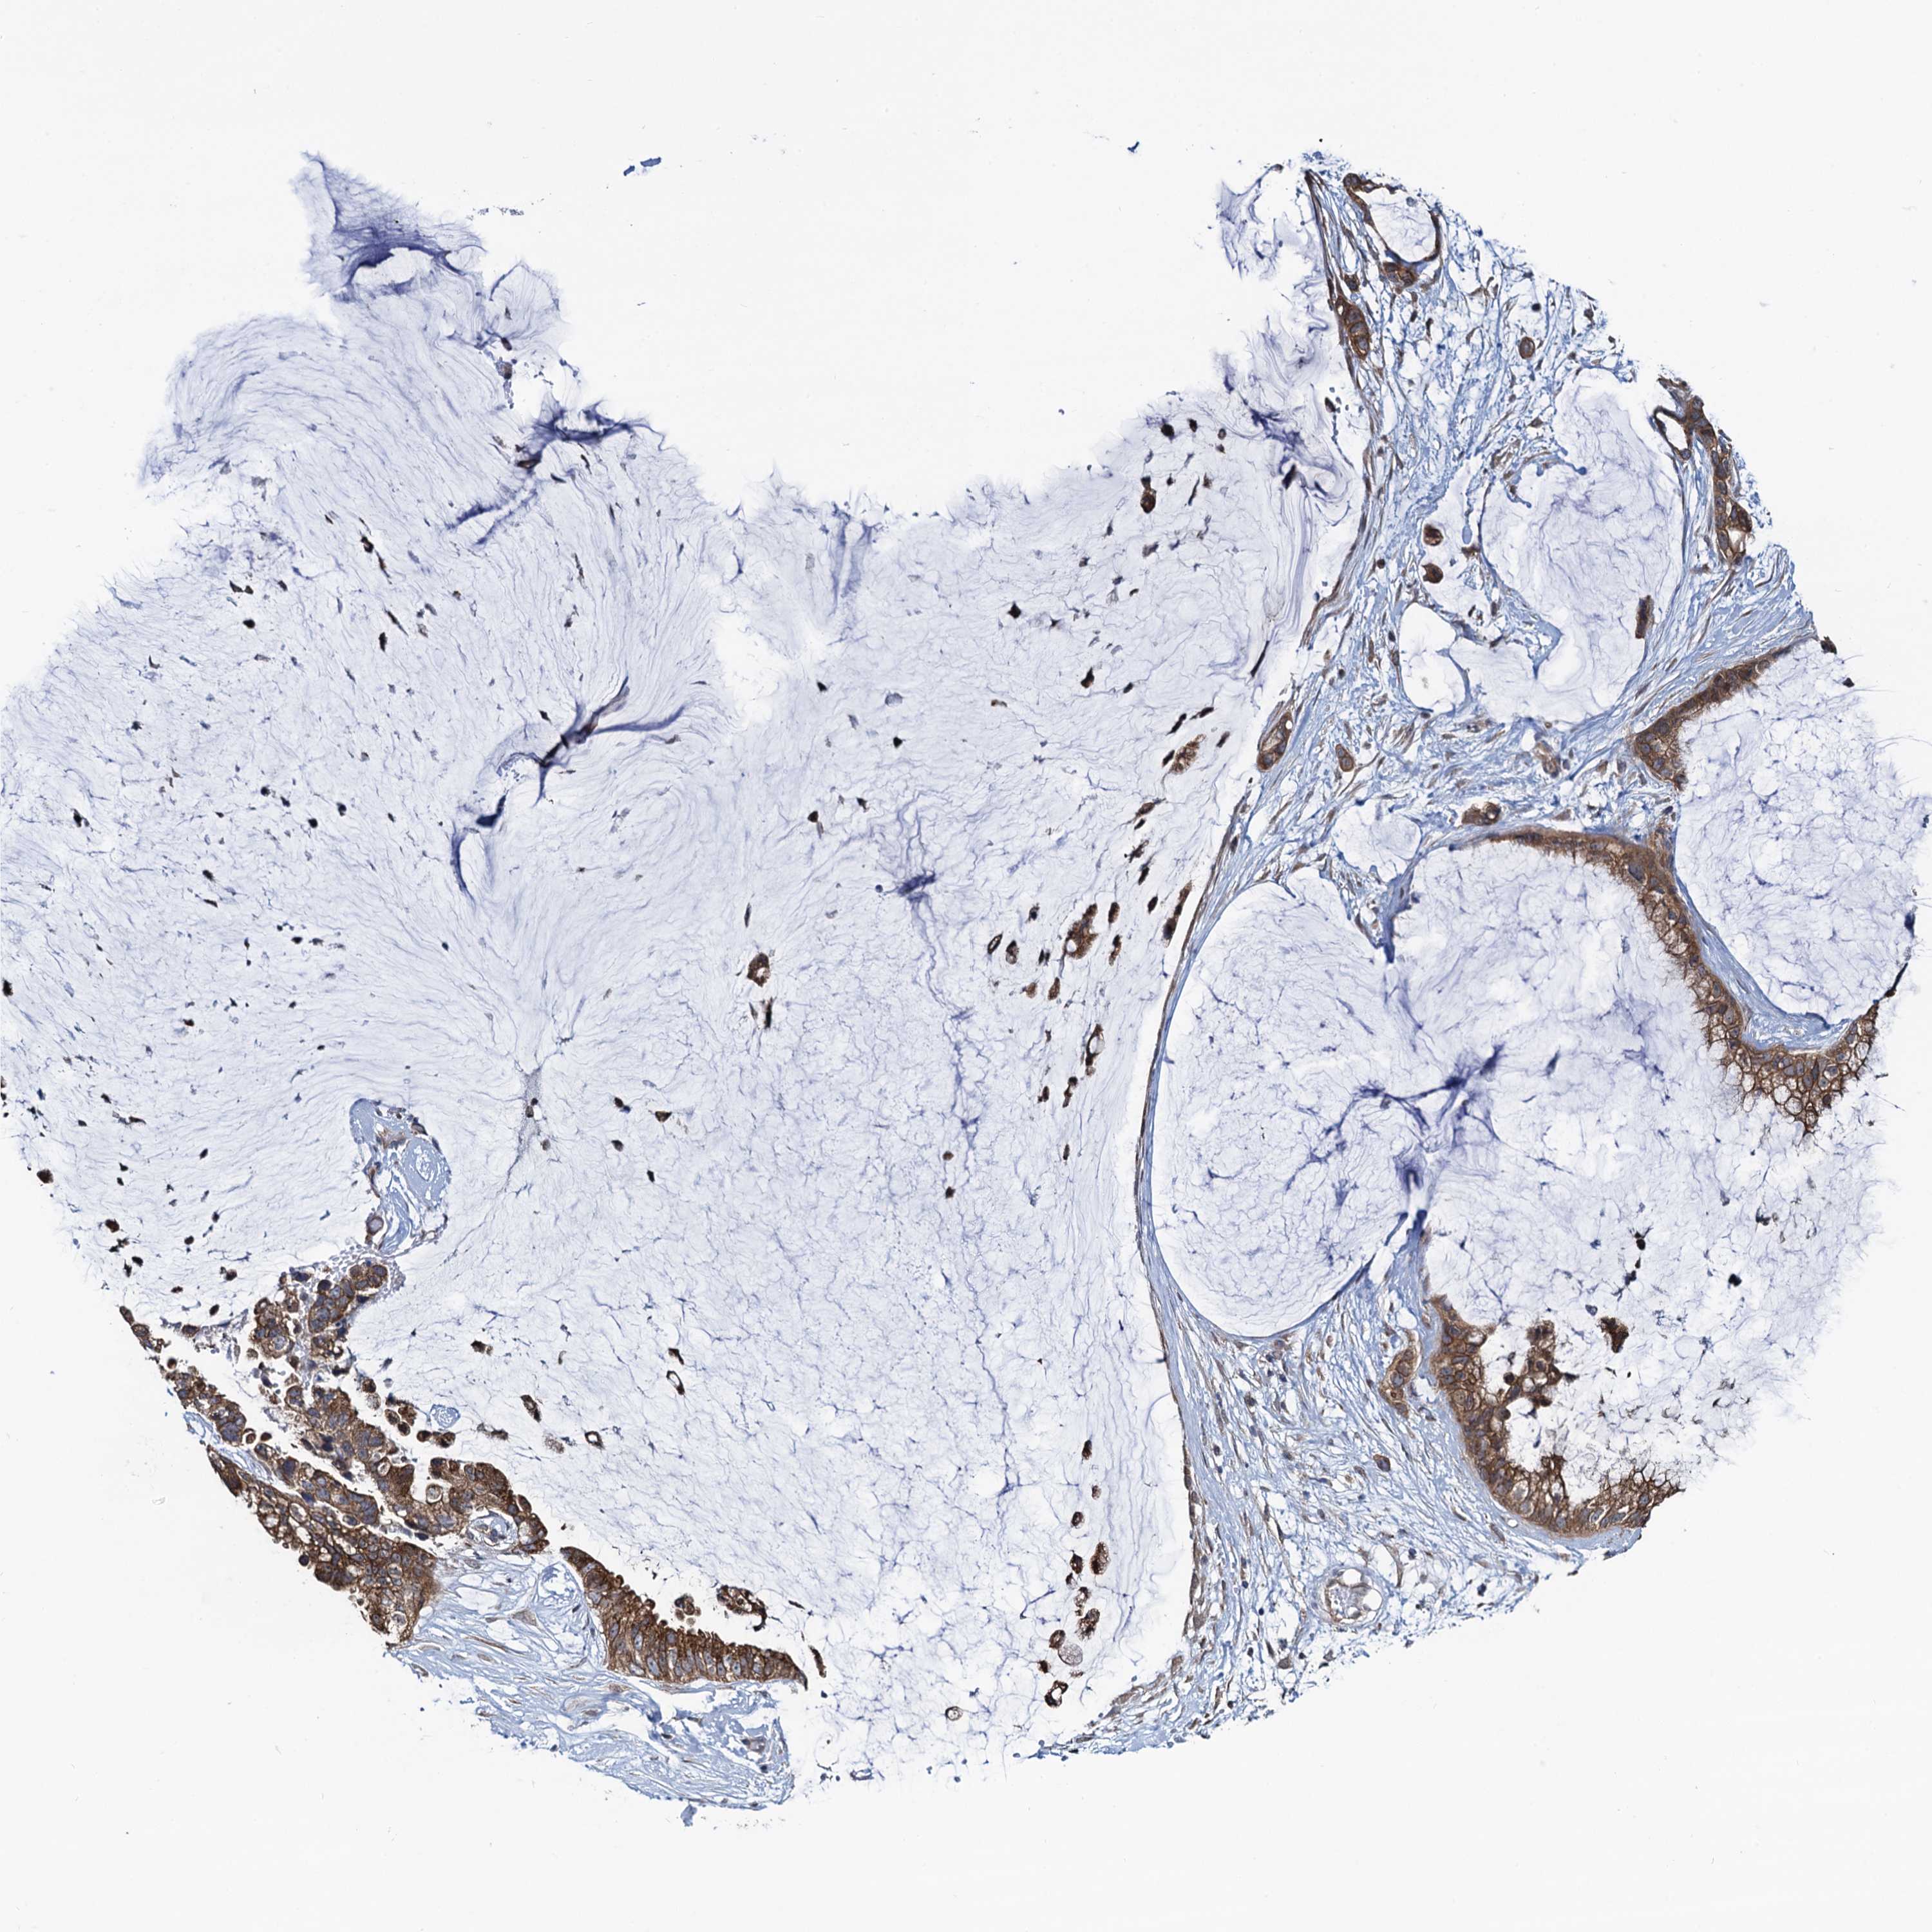

OVARIAN CANCER - Protein expressioni

A mouse-over function shows sample information and annotation data. Click on an image to view it in a full screen mode. Samples can be filtered based on level of antibody staining by selecting one or several of the following categories: high, medium, low and not detected. The assay and annotation is described here.

Note that samples used for immunohistochemistry by the Human Protein Atlas do not correspond to samples in the TCGA dataset.

Antibody stainingi

Antibody staining in the annotated cell types in the current human tissue is reported as not detected, low, medium, or high, based on conventional immunohistochemistry profiling in selected tissues. This score is based on the combination of the staining intensity and fraction of stained cells.

Each image is clickable and will lead to virtual microscopy that enables deeper exploration of all samples and also displays staining intensity scores, fraction scores and subcellular localization as well as patient and tissue information for each sample.

Antibody HPA041514

Staining

High

Medium

Low

Not detected

Intensity

Strong

Moderate

Weak

Negative

Quantity

>75%

75%-25%

<25%

None

Location

Nuclear

Cytoplasmic/membranous

Cytoplasmic/membranous,nuclear

Cystadenocarcinoma, serous, NOS

Carcinoma, endometroid

Cystadenocarcinoma, mucinous, NOS

Carcinoma, NOS